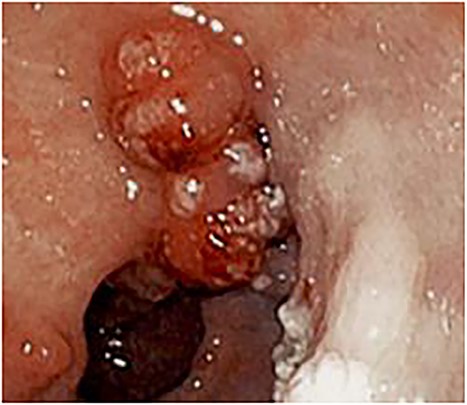

Esophagogastroduodenoscopy revealed varices in the esophagus as well as the gastric cardia and fundus. Multiple 10–20 mm sessile polyps were also present in the prepyloric and antral regions with some associated pseudomembranous-like exudate (Fig. 1).

Endoscopy showing 10–20 mm sessile polyps and pseudomembranous-like gray-white exudate overlying the gastric mucosa in the prepyloric and antral regions of stomach.